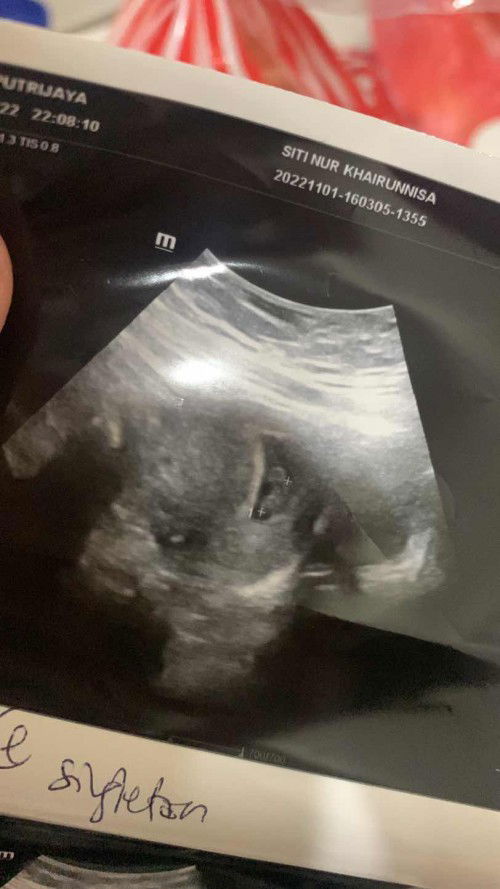

Scan semula after 2 weeks

Alhamdulilah 😍 Doctor kata hari tu kandungan saya baru 5 weeks sedangkan saya dah 7 weeks But after comeback 2 weeks alhamdulilah i see hearbeat dia 🥹 baby i waiting you lama sangat tau So guys kalau scan bukan dari usia kandungan korang sepatutnya jangan risau dan sedih, tetap semangat korang doa banyak2